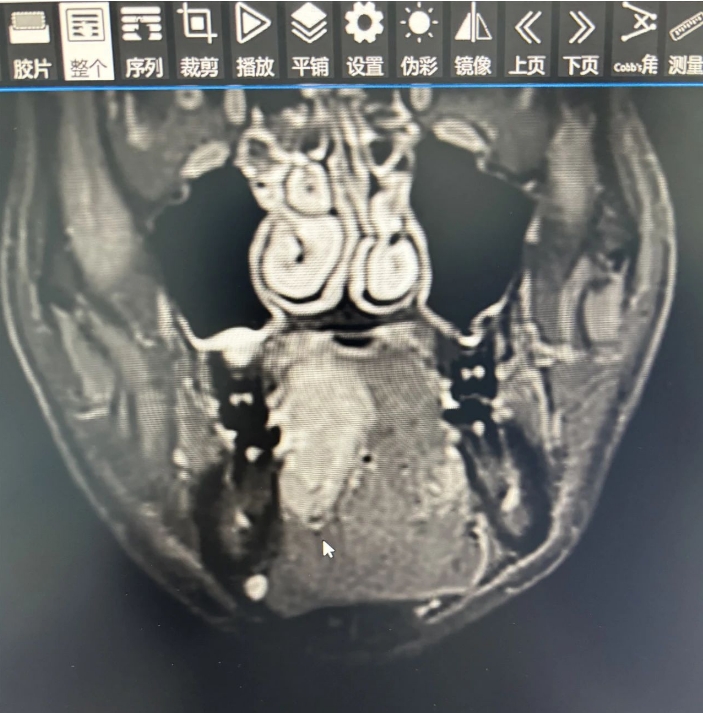

42岁的何先生长期咀嚼槟榔,近两个月以来,发现右侧舌腹肿痛不适,遂前往湘南学院附属医院就诊。经口腔科完善相关检查,确诊了何先生罹患舌癌。

舌恶性肿瘤是口腔恶性肿瘤里发病率占比最高的,也是最容易发生转移的,目前最适宜的治疗手段就是尽早发现、尽早治疗,以防转移后手术效果欠佳。

口腔科团队为何先生展开了详细的术前讨论,并想方设法从各方面为患者节约治疗费用,做好了充分的术前准备后,为何先生实施了舌颌颈联合根治术+股前外侧肌皮瓣转移修复术。

此项手术是一项高难度、极具挑战性的手术,需要完成颈部淋巴结的切除、口腔恶性肿瘤的切除、制备皮瓣、吻合血管及颌面部重建四大步骤,每一步都需要耗费医务人员大量的精力和时间,常规需要12小时左右才能完成。